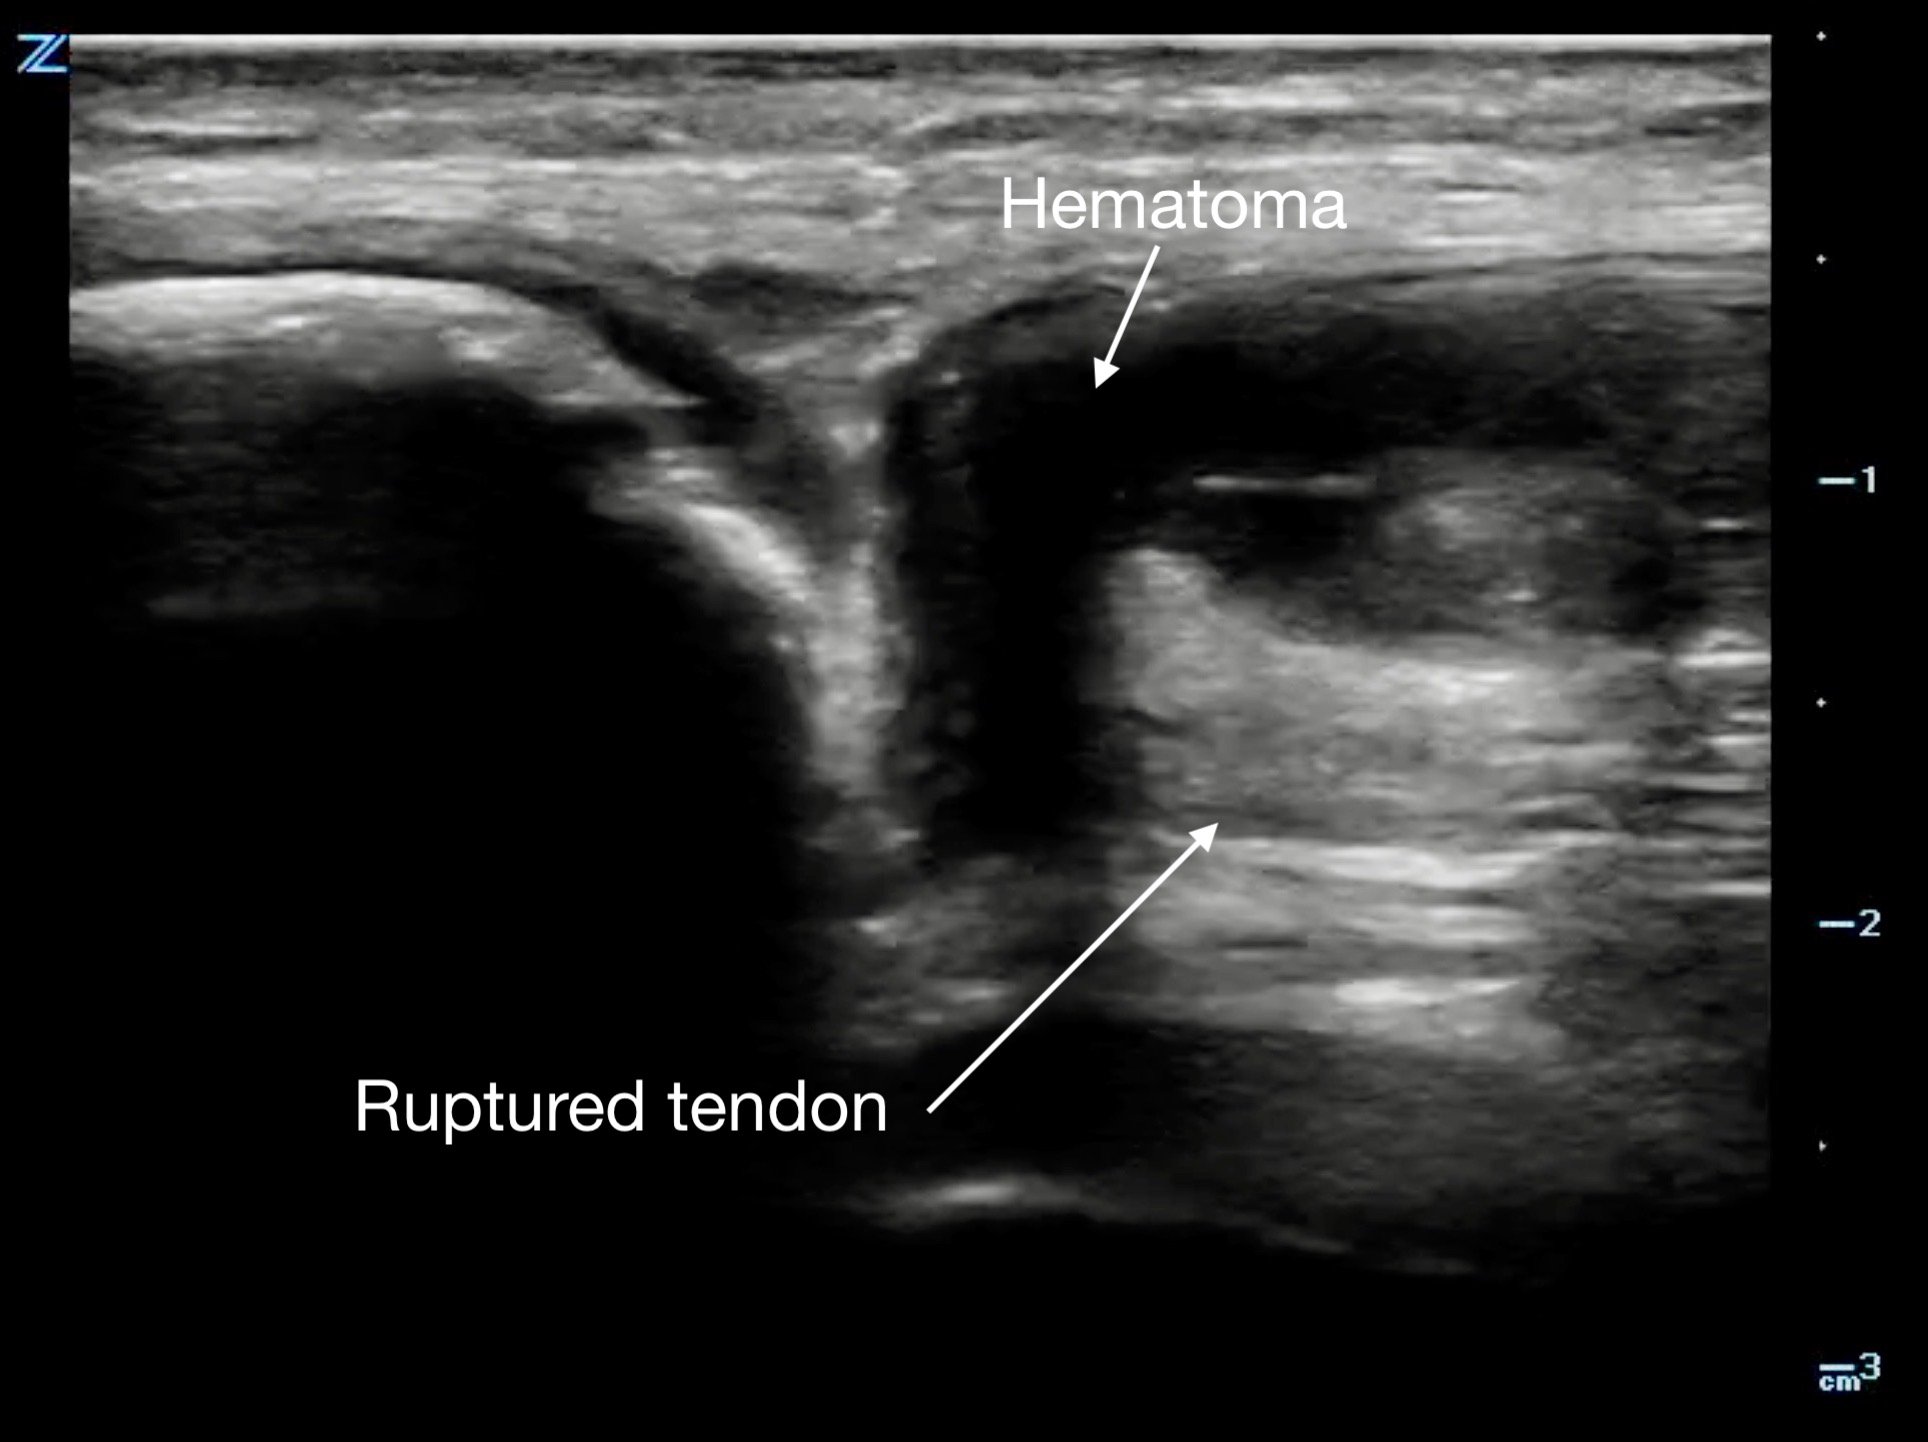

Tendon ruptures appear as areas of hypoechogenicity from edema/hematoma, and adjacent bunched up, retracted tendon fibers. For complete tears, the portion of the tendon near the injury will lose its rigid, straight appearance and instead appear irregular and have a large gap between the torn end and its insertion point. Partial tears are more subtle and will sometimes only have a small, cone-shaped hypoechoic focus. The key with tendon exams is to view them dynamically, having the patient flex and extend the injured joint (if possible).

Figure 13a.

A) Partial rupture of the patellar ligament at the distal insertion

Figure 13b.

a different patient with a complete rupture at the proximal insertion of the patellar tendon. The patella is on the left side of the image, and note the hematoma that wraps around the ruptured end of the tendo